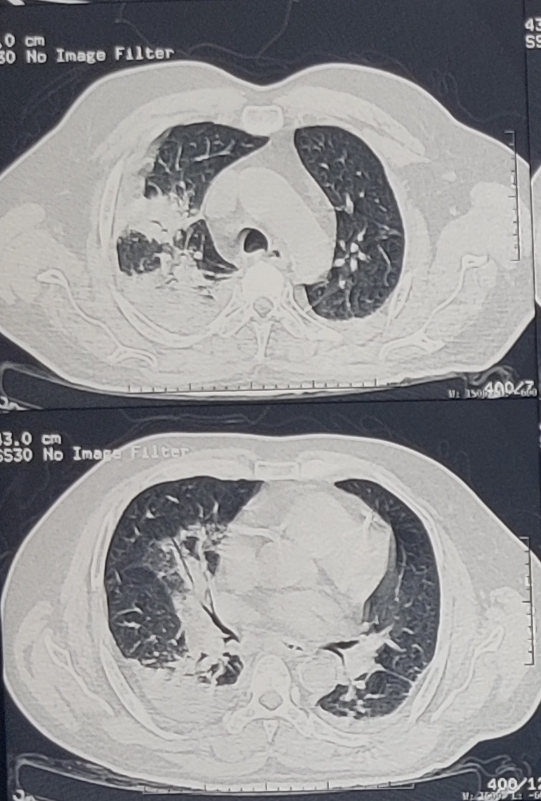

HRCT REPORT THORAX:

CT PULMONARY ANGIOGRAM -

CTPA (26/6/23)